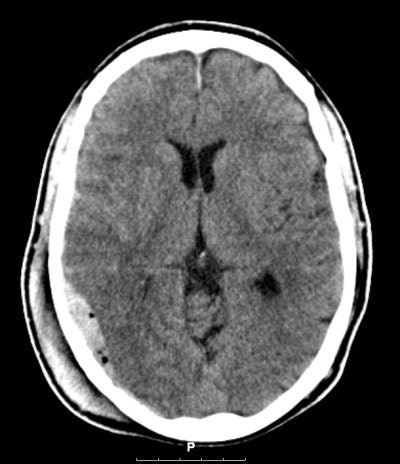

![]() |

| Routine CT scanning may still be the best option for patients with minor head injury. Image courtesy of Dr. Marion Smits. |

CT scans are used routinely regardless of cost for timely diagnosis of neurocranial complications in patients presenting with MHI. But the cost of such routine scanning has prompted clinicians and public health advocates to try to find ways to be more selective about who gets scanned.

If the sensitivity of selective strategies falls to less than 91%, which is quite feasible given that more than 90% of MHI patient CT scans are "normal" (i.e., show no signs of traumatic abnormality), routine CT scanning becomes the clear dominant strategy, she said.